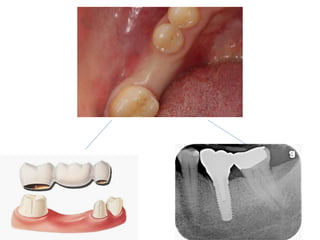

1.Difference between tooth

supported and implant supported

restorations

Tooth-supported

Implant-supported

Preservation of

tooth structure

NO YES

Transmission of

forces to bone

Less More

(if not performed

properly)

Bone loss More (Pontic area) Less (if performed

Maintenance by

patient

Difficult Easy

Time of fabrication Short Long

Cost less expensive More expensive

Service life 7-10 years Up to 20 years